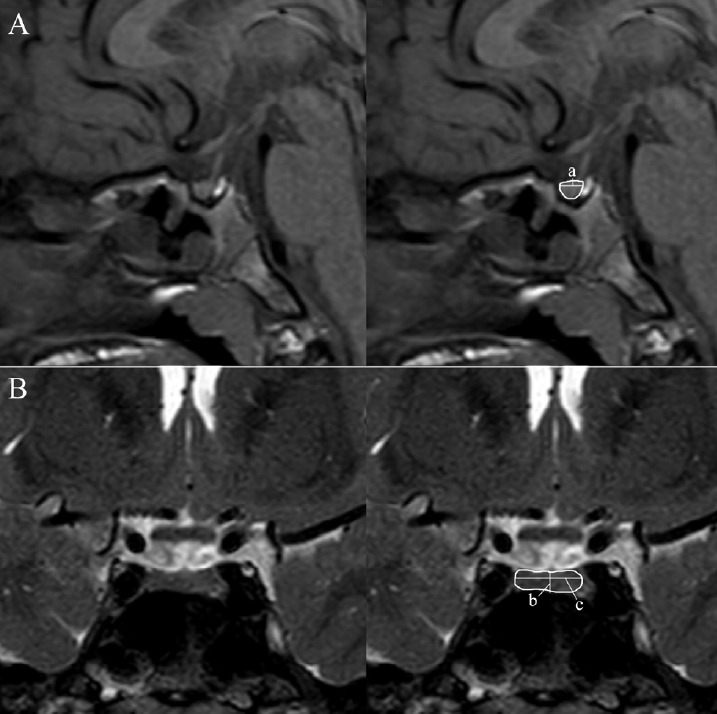

Purpose: Magnetic resonance imaging (MRI) can be used for assessing the morphology of the pituitary gland in children with short stature. The purposes of this study were: (1) to determine if pituitary volume (PV) can distinguish patients with growth hormone (GH) deficiency from those with idiopathic short stature (ISS), (2) to validate an association between PV and severity of GH deficiency, and (3) to compare PV between good and poor response groups in children with GH deficiency or ISS after 1 year of treatment.

Methods: Data were collected from the medical records of 152 children with GH deficiency or ISS who underwent GH stimulation test, sella MRI, and GH treatment for at least 1 year. Estimated PVs were calculated using the formula of an ellipsoid. We compared the PVs in patients with GH deficiency with those of patients with ISS. In addition, we assessed the association between PV and severity of GH deficiency, and we assessed growth response after treatment.

Results: No difference was observed in PV between patients with GH deficiency and those with ISS. The severity of the GH deficiency seemed to be associated with PV (P=0.082), and the height of the pituitary gland was associated with severity of GH deficiency (P<0.005). The PV in the good response group was less than that of the poor response group in patients with GH deficiency (P<0.005), and PV showed no association with responsiveness to GH treatment in patients with ISS (P=0.073).

Conclusion: The measurement of PV cannot be used for differential diagnosis between GH deficiency and ISS. In patients with GH deficiency, PV tended to be smaller as the severity of GH deficiency increased, but the difference was not significant. PV may be a good response predictor for GH treatment. Further studies, including a radiomics-based approach, will be helpful in elucidating the clinical implications of pituitary morphology in patients with short stature.